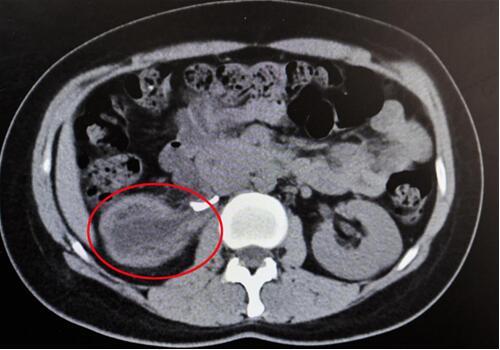

紅圈部分為手術(shù)后腎臟輪廓逐漸清晰。院方供圖

手術(shù)原理并不復雜,找到并切掉閉鎖的輸尿管,再將健康的輸尿管重新接起來即可,但看似簡單,做起來卻并不容易。首先使用輸尿管鏡給患者檢查,醫(yī)生發(fā)現(xiàn)輸尿管鏡前進10cm左右無法繼續(xù)上行,此處的輸尿管已經(jīng)完全閉鎖了。于是醫(yī)生在患者右下腹部切開一個5公分的切口,逐層揭開進入腹膜后間隙,開始尋找閉鎖的輸尿管。

“但因為患者周圍組織粘連嚴重,輸尿管界限不清,僅僅是尋找輸尿管,我們就差不多花了4個小時!苯纳魅伪硎,整臺手術(shù)花了近6個小時,大部分的時間都花在了尋找輸尿管這個過程中,“‘拆除’閉鎖的輸尿管這顆‘炸彈’是保腎的唯一方法,如果輸尿管接不通,這個腎臟將難逃被切除的命運!苯纳魅握f,因而,即使多次想要放棄,他們依然互相鼓勵“再咬咬牙,再試一次”。

終于,功夫不負有心人,他們在粘連嚴重的腹膜外組織中找到了輸尿管!當時,靳文生主任心里緊繃的一根弦終于松了下來,接下來的手術(shù)過程也變得順暢了。